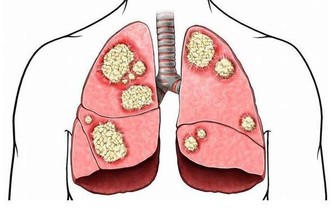

①生理病理需要:兒童、老人、孕婦及哺乳期婦女,以及有消耗性疾病如惡性腫瘤、肺部感染、瘧疾等患者,對某些維生素的需求超過常人。